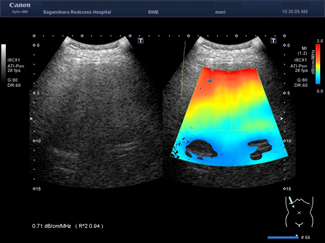

フィリップス、「Liver Fat Quantification(肝脂肪化定量評価。肝臓がん|消化器|診療内容|医療法人 甘木第一クリニック。肝臓がん|消化器|診療内容|医療法人 甘木第一クリニック。sakuraさん専用 蔵王吊るし柿4kg 紅干し柿 600g。Contrast Enhanced Ultrasound (CEUS) | フィリップスヘルスケア。Liver Ultrasonography | SpringerLink。キヤノンメディカルシステムズ、『肝臓の脂肪量の汎用超音波画像。Imaging Features of Hepatocellular Carcinoma in the Non。Imaging Features of Hepatocellular Carcinoma in the Non。714cFtk9QyL._AC_UF350,。肝臓病変における超音波の最新情報-第24回腹部放射線研究会。KMS_M01_XXX_670.jpg。腹部の超音波検査健康なヒト胆嚢 - 胆嚢のストックフォトや画像。